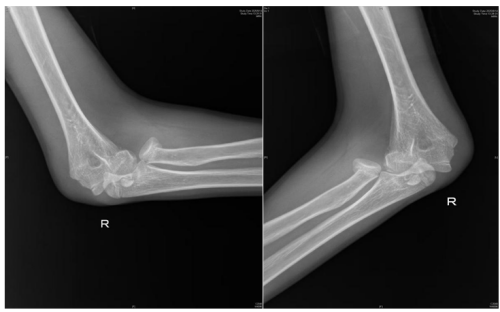

术前检查提示桡骨头骨折,肱骨远端骨折,肘关节脱位

人体的肘关节就像一座精密的“协作工厂”,里面住着三位重要“伙伴”—桡骨、尺骨和肱骨。桡骨顶端有一个像“小圆帽”的结构,那就是桡骨头。它相当于肘关节的“旋转轴承”,帮助我们完成转笔、拧瓶盖、拧毛巾等需要前臂旋转的动作。蒋亮东提醒,当我们低头紧盯手机屏幕,不仅注意力高度集中,身体平衡能力也会下降。一旦不慎跌倒,手会本能地支撑地面。此时巨大冲击力会沿手臂向上传导,如同“冲击波”一般直击桡骨头这个“小圆帽”,轻则使其裂缝,重则崩碎成数块。通过X光片,医生可以清晰地看到它的“受伤模样”。